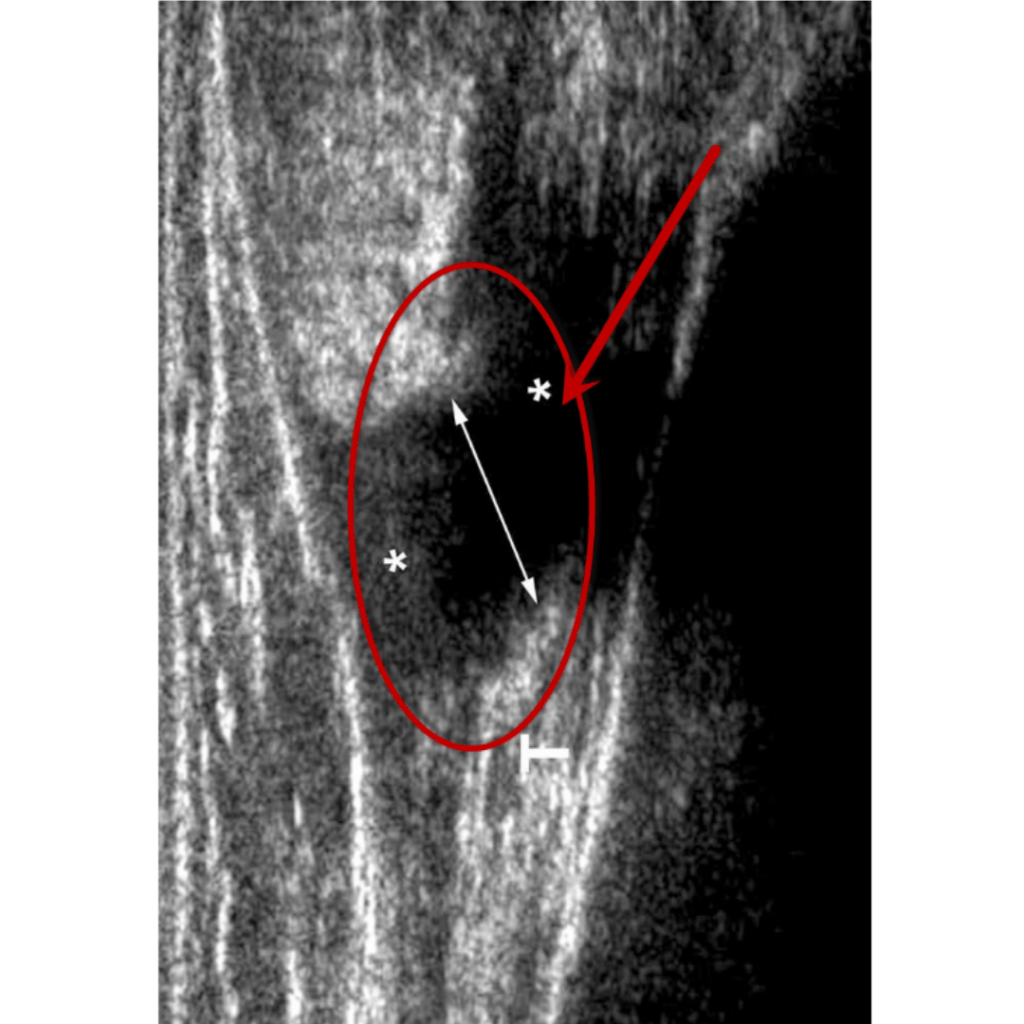

El diagnóstico de esta afectación dependerá mucho de su localización, en caso de sospecha de compromiso en un músculo superficial se puede hacer uso de ecografía (ultrasonido), en tejidos más profundos es más eficiente una resonancia magnética.

Ultrasonido

Ruptura total Grado III

Un desgarro de segundo grado en el gemelo medial (músculo de la parte interna de la pantorrilla) el cual no necesito un tratamiento quirúrgico.Por lo que fue referido para su recuperación con terapia física.